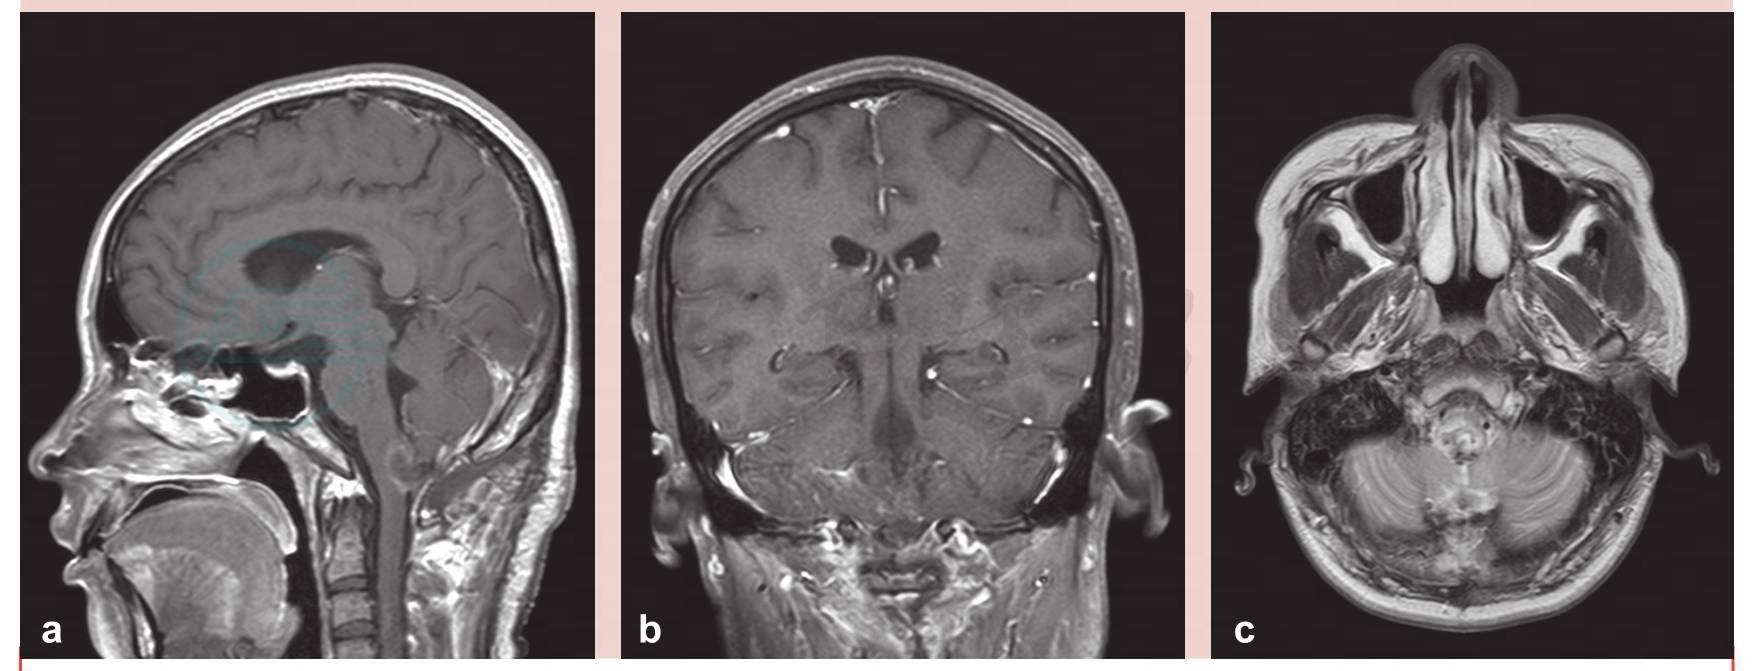

患者术后第1天拔除气管插管,自主呼吸平稳,无吞咽障碍。间断行腰椎穿刺2次,释放脑脊液。左上肢麻木感减轻,左上肢远端肌力Ⅳ级,右上肢浅感觉减弱。术后增强MRI扫描提示病变切除满意(图5)。术后10天顺利出院,于当地康复医院行后续康复治疗。

图5 术后增强磁共振(MRI)扫描提示病变切除满意

a.矢状位;b.冠状位;c.轴位